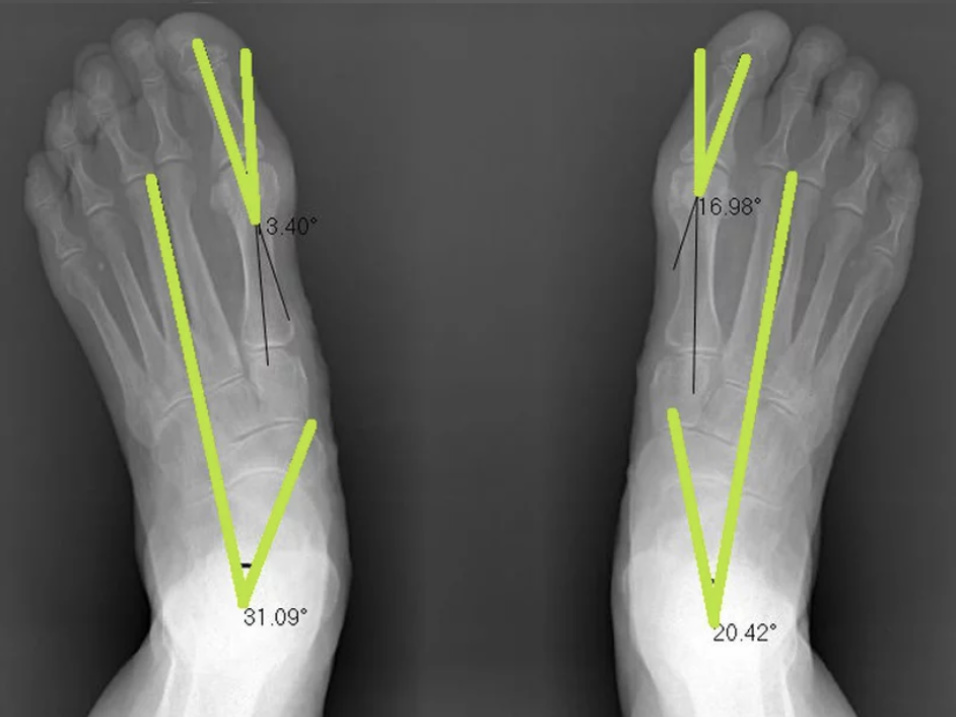

Below is Margaret Perry's before and after x-rays. Margaret had tried orthotics but found they were extremely limiting as they didn't fit in her shoes and didn't improve her foot pains.

We completed a course of Foot Mobilisation Therapy, which is a hands on technique that gently corrects the alignment of the foot and lower leg.

You can clearly see the joint misalignment has improved and she is standing straighter . Her bunion angles have reduced and the bone (talus) in her ankle has repositioned into a normal position which is between 12-18 degrees!